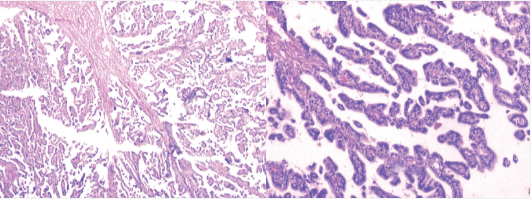

顯微照片顯示纖維血管核心的多個(gè)乳頭狀結(jié)構(gòu)(左)、乳頭狀結(jié)構(gòu)排列整齊的立方至柱狀上皮細(xì)胞(右)

魯特卡教授通過(guò)右頂骨開顱手術(shù)和側(cè)腦室切開后中央回后方的皮質(zhì)切口。暴露血管高度豐富的腫瘤,夾緊蒂部并燒灼,然后順利切除腫瘤。術(shù)后病理結(jié)果顯示為脈絡(luò)叢乳頭狀瘤。